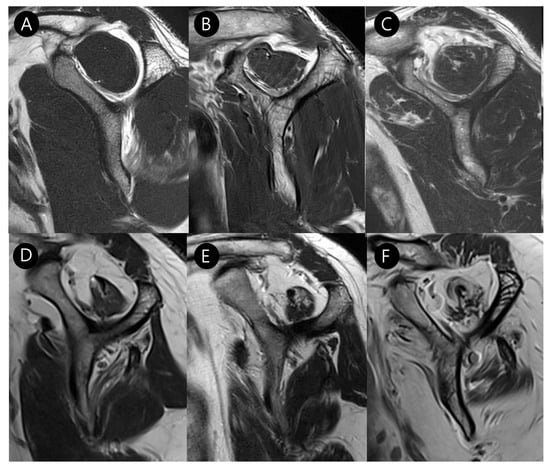

Subscapularis muscle atrophy was evaluated using the Warner classification [12] and the method described by Seppel et al. [13]. The muscle area of the subscapularis was measured in the “Y-position” on the oblique sagittal plane, defined as the most lateral image where the scapular spine contacts the body of the scapula. A virtual reference line was drawn from the superior border of the coracoid process to the inferior margin of the subscapularis muscle at the level of the scapular inferior tip, parallel to the long axis of the scapular body (Figure 4). If the muscle is convex above the line, there is no atrophy. If the muscle contour is even with the line, mild atrophy exists. If the contour of the muscle is concave below the line, moderate atrophy is present. If there is barely any muscle visible, severe atrophy exists [12]. For statistical analysis, we categorized muscle atrophy into two categories: non-mild and moderate–severe degrees.

Figure 4.

Evaluation of subscapularis muscle atrophy on T2-weighted oblique sagittal images. The grade is determined by the amount of muscle above or below a virtual line (green dashed line) drawn from the superior border of the coracoid process to the inferior margin of the subscapularis muscle at the level of the scapular inferior tip (solid line), parallel to the long axis of the scapular body (double-headed arrow). (A) None, (B) Mild atrophy, (C) Moderate atrophy, and (D) Severe atrophy.